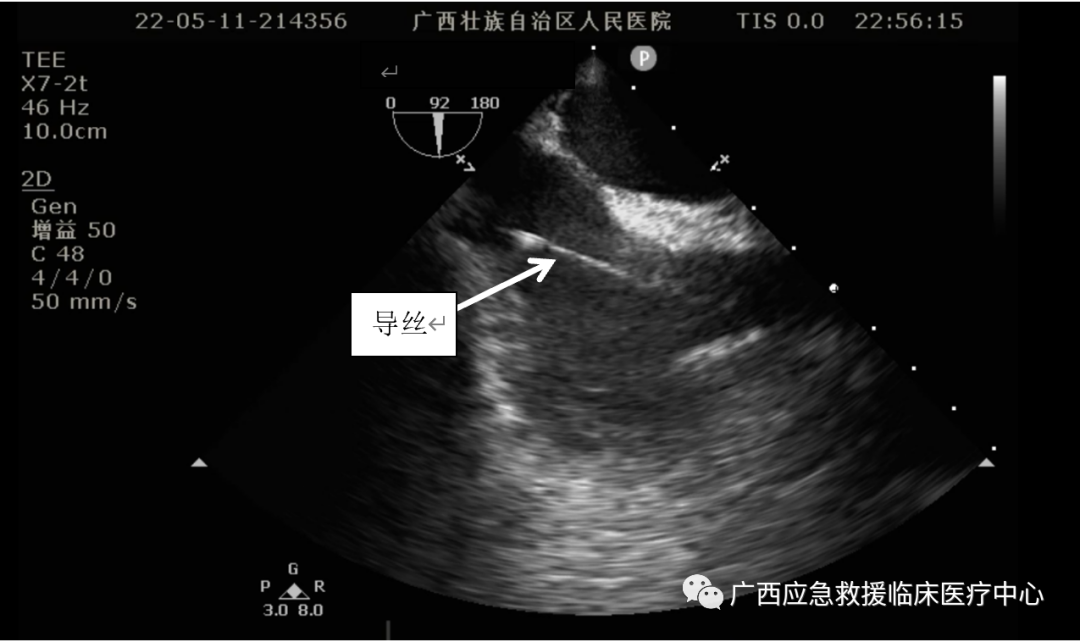

食道超声引导下进行Crescent置管及定位:

食道超声引导导丝